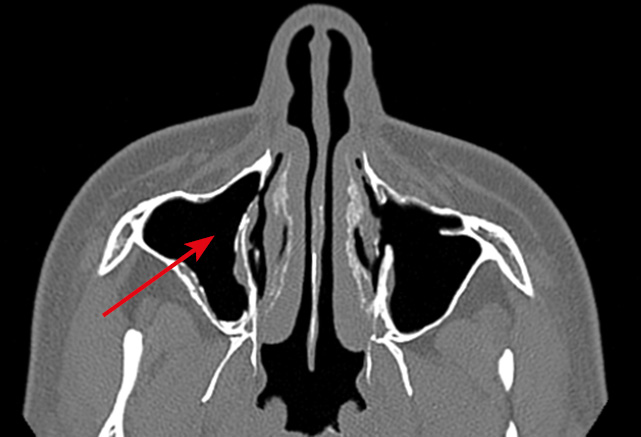

Облитерация СОП на уровне нижней трети НСК возникала также у пациентов после таких хирургических вмешательств, как различные виды конхопластик нижних носовых раковин (6 случаев). В двух случаях облитерация устья НСП сформировалась после выкраивания лоскутов в области нижнего носового хода: с целью пластического закрытия перфорации перегородки носа (1 случай, рис. 5), а также при проведении инфратурбинальной антростомии (1 случай, рис. 6). По данным МСКТ костная часть НСК у этих пациентов оставалась интактной. При планировании вмешательства в нижнем носовом ходе целесообразно определить локализацию устья НСП, во избежание его травматизации. В случаях недостаточной визуализации устья НСП возможна его идентификация при промывании СОП, в том числе с использованием красителя [25].

Рис. 5. Случай неудачной попытки пластики перфорации перегородки носа. Развитие вторичного дакриоцистита с частичной проходимостью носослезного протока (OS) после забора лоскута слизистой оболочки в области нижнего носового хода слева, формирование дакриостеноза на уровне устья носослезного протока (стрелка)

Fig. 5. A case of plasty failure for nasal septal perforation. Secondary dacryocystitis with partial patency of the nasolacrimal duct (OS) after dissection of a mucosal flap in the left inferior nasal passage, dacryostenosis at the level of the nasolacrimal orifice (arrow)

Рис. 6. Хронический дакриоцистит (OD) с частичной проходимостью носослезного протока после гайморотомии, дакриостеноз носослезного канала на уровне нижней трети (стрелки)

Fig. 6. Chronic dacryocystitis (OD) with partial patency of the nasolacrimal duct after maxillary sinusotomy, dacryostenosis of the nasolacrimal duct at the level of the lower third (arrows)